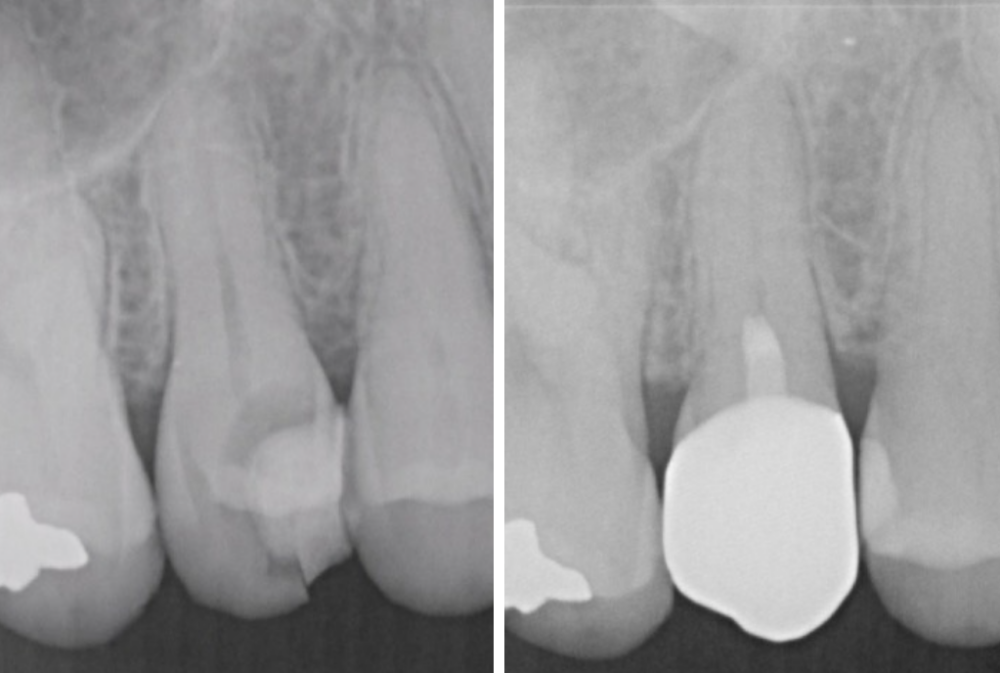

症例2

| 患者様データ | 30代 男性 |

| 来院時の主訴 | 「右上の歯が何もしなくても痛い。他院で神経を取ると言われたが、残せないか相談したい。(セカンドオピニオン)」 |

| 術前検査結果 | 歯髄の生活反応有り、自覚症状有り |

| 医院の診断 | 症候性可逆性歯髄炎 |

| 治療費 | 総額:197,000円(税抜) 【内訳】 セカンドオピニオン20,000円、歯髄保存療法(MTA使用)55,000円、セラミック治療120,000円、術後経過観察時検査代1,000円×2回分 |

| ここがこだわりのポイント!☝ | 術前の症状の強さは神経を残せるかどうかには関係ありません。術前検査情報に加えて、術中のマイクロスコープでの歯髄診査にて神経を残せるかどうかの最終判断を行なっています。 |